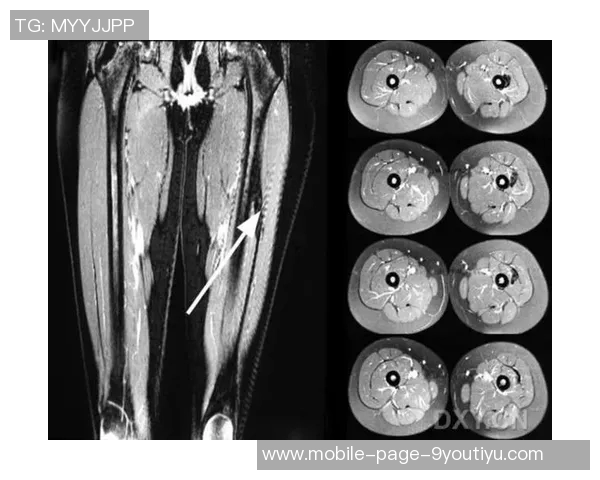

为了进一步确认诊断,医生建议进行了影像学检查,包括MRI扫描。结果显示右大腿后群肌纤维部分撕裂,同时伴随周围组织水肿现象。这种情况符合I级肌筋膜炎,即轻度损伤,但仍需认真对待,以免延误康复过程。

综合以上症状及检查结果,可以确诊为右大腿后群肌肉拉伤及肌筋膜炎I级。对此,需要制定科学合理的治疗方案,以帮助李磊早日恢复正常运动功能。